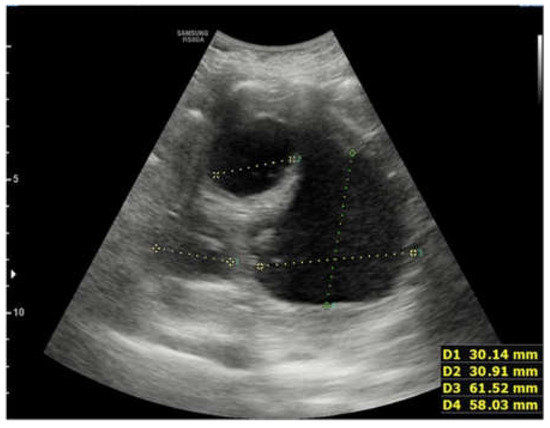

2. Case Report